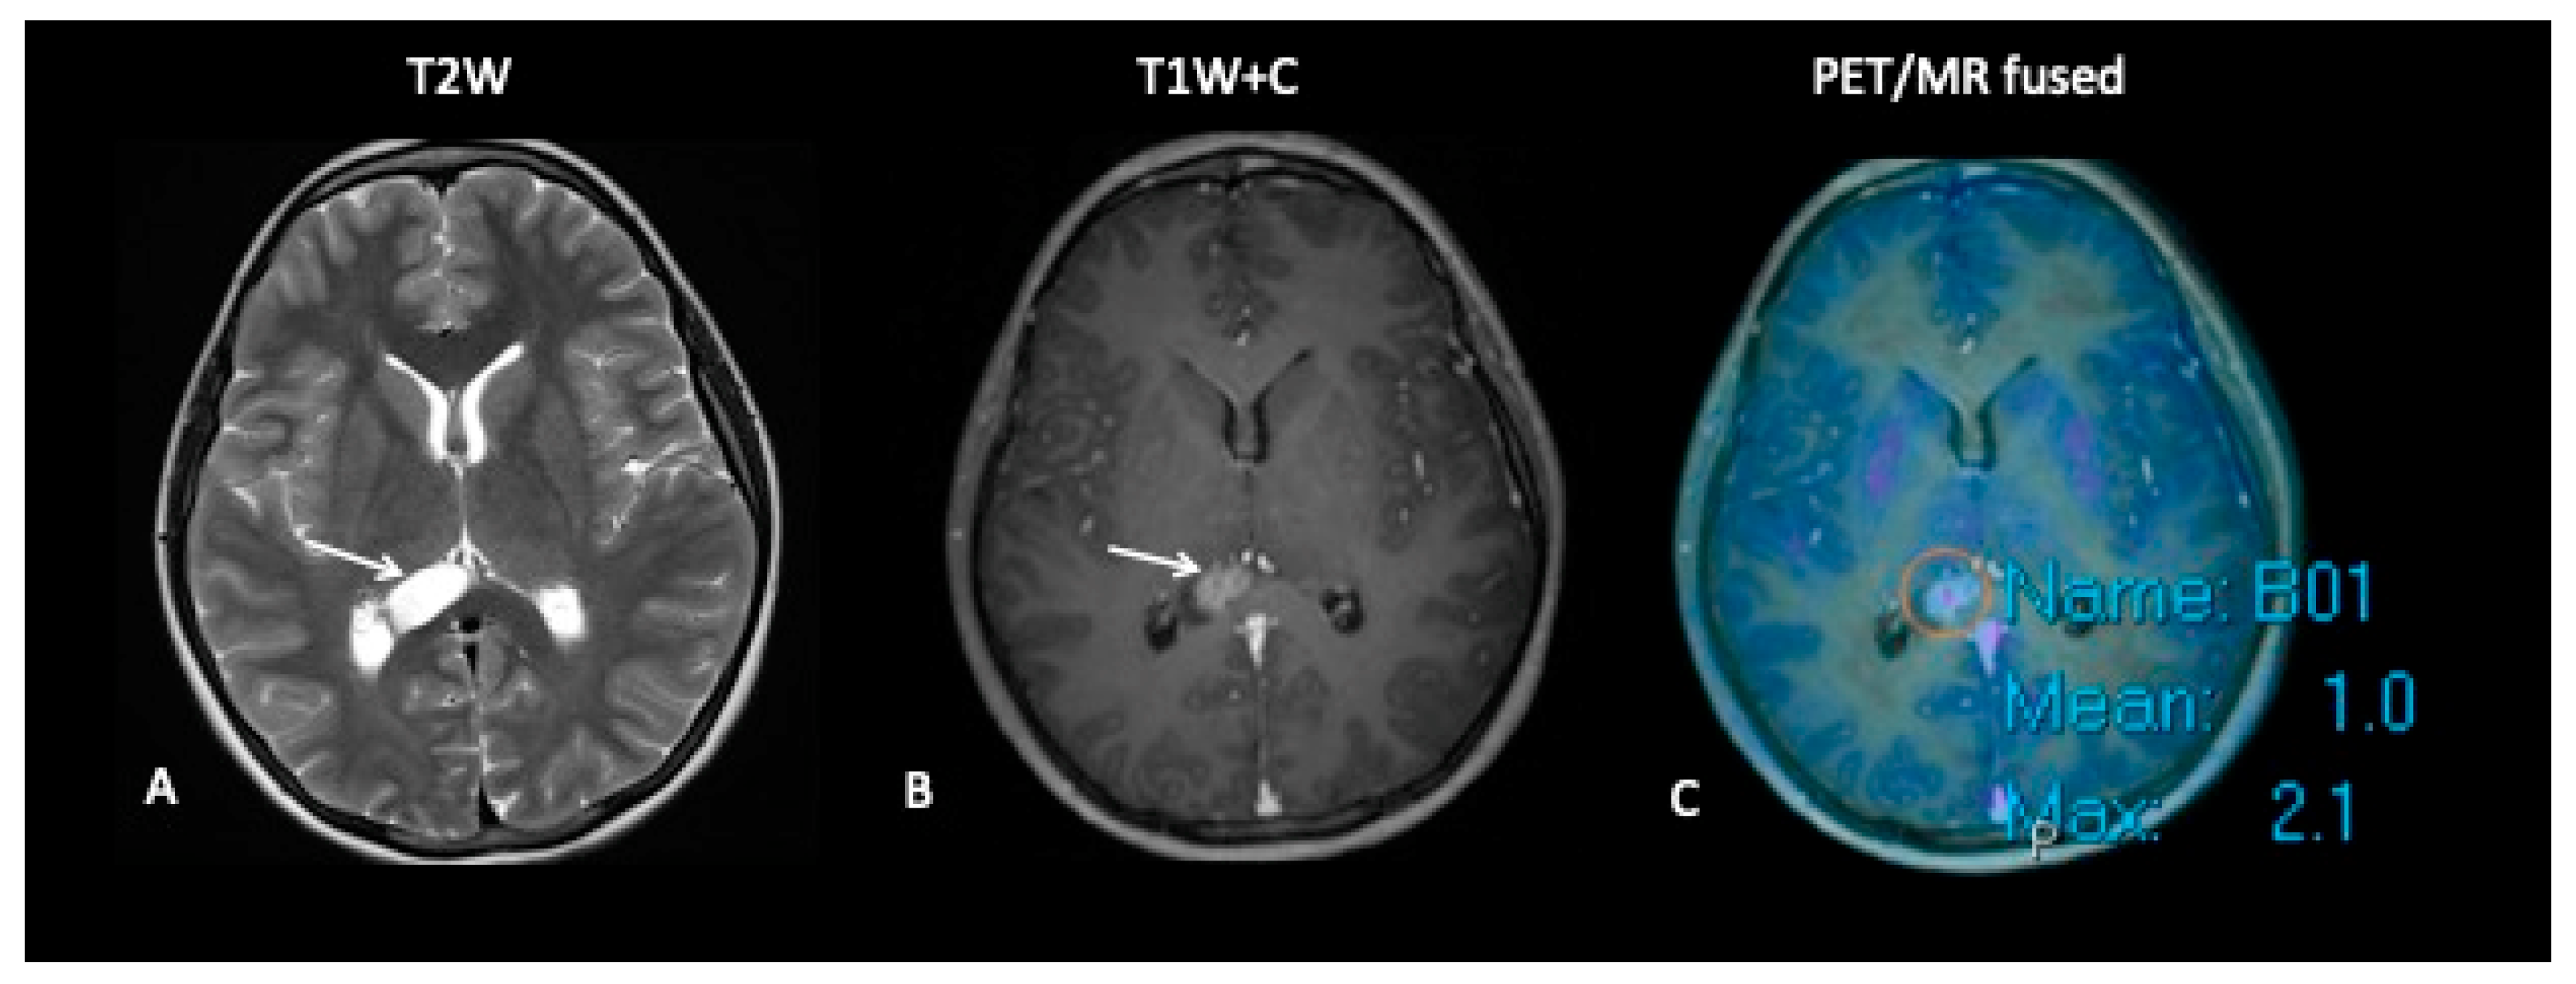

- Patient 4: Tumour Progression Versus Pseudoprogression

A 15-year-old male with a large tumour involving the left thalamus underwent gross resection of the thalamic tumour, and the histology confirmed this to be a high-grade astrocytoma with the known histone H3F3A K27M mutation. A response assessment scan after 6 months of chemotherapy (Figure 7) suggested minimal enhancement in the residual tumour that was thought to be pseudoprogression. However, FDOPA showed tracer uptake consistent with tumour progression.

Figure 7.

The baseline imaging post-surgery demonstrates residual non-enhancing tumour in the medial right thalamus (A–C). Follow-up imaging demonstrates the non-enhancing component (D) and mild enhancement of this component (E), uncertain for tumour progression or pseudoprogression, but the FDOPA (F) demonstrates increased uptake consistent with tumour progression.